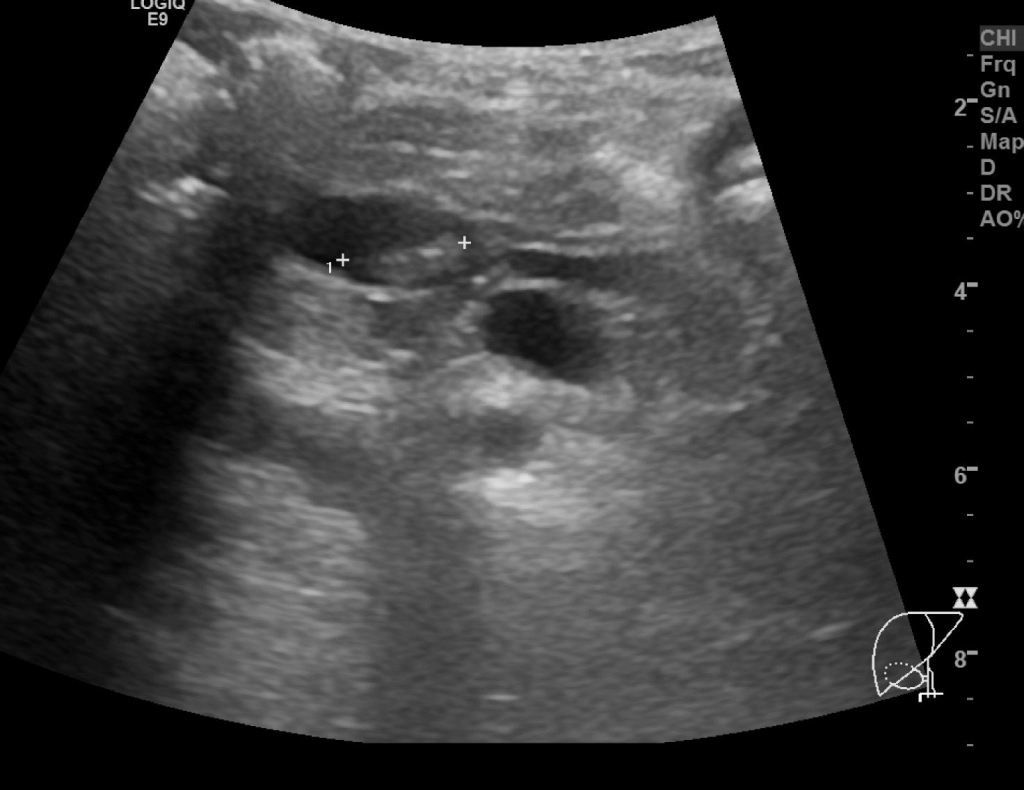

같은 총수담관내 결석을 횡단면 스캔영상으로 확인했습니다. 뚜렷한 후방에코음영을 동반한 결석을 확인할 수 있습니다.